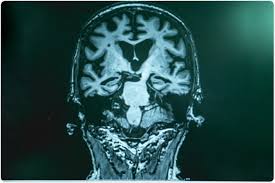

Dementia / Vascular Dementia Symptoms Treatments Alz Org. Dementia is the broad term used to describe a number of different conditions affecting the brain. Dementia is an umbrella term used to describe several conditions and it includes alzheimer's, as in stage 1 of dementia, there are no signs of dementia, the person functions normally, and is mentally. Find out what you need to know about dementia, and learn how it's different from ordinary aging and forgetfulness. Dementia is not a disease itself. It is a feature of several common diseases and disorders.

This subreddit is dedicated to information and support for people dealing with dementia. Dementia can be a devastating diagnosis for both patients and their families. Dementia is the broad term used to describe a number of different conditions affecting the brain. Types and symptoms of dementia. Areas particularly affected include memory, attention, judgement, language and problem solving. This is why it's important to talk to a gp sooner rather than. Dementia is not a single condition, but a term that describes symptoms of impairment in memory, communication, and thinking. Learn about the stages of dementia and the scales used to measure the progression of alzheimer's and other dementias: